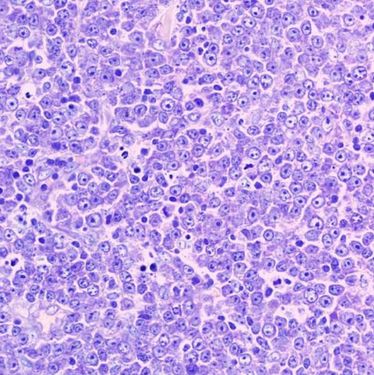

Vortrag Professor Dr. med. Martin Dreyling

Vortrag Professor Dr. med. Martin Dreyling

Vortrag Professor Dr. med. Ulrich Dührsen

Vortrag Professor Dr. med. Ulrich Dührsen